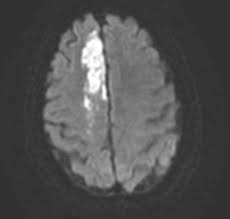

Stroke Neupsy Key from neupsykey.com Fast (face, arm, speech, time) has a sensitivity of 82% and a specifity of 83%. Stroke mechanisms and clinical features of anterior cerebral artery (aca) territory infarction have rarely been investigated using mri. Clinical, mri, and angiographic findings of 100 consecutive patients with aca infarction were studied. We studied the topographical distribution of the lesions and the resulting clinical effects for a better understanding of their relationship and the functional outcome. The internet stroke center n.d.b) anterior cerebral artery stroke. It is characterized by weakness and sensory loss in the lower leg and foot opposite to the lesion and behavioral changes. The mean age of the cohort was 71 years. The anterior inferior cerebellar artery (aica) is responsible for carrying blood to the cerebellum.

Anterior cerebral artery syndrome refers to symptoms that follow a stroke occurring in the area normally supplied by one of the arteries. If the anterior inferior cerebellar artery becomes blocked, a stroke can occur. Stroke mechanisms and clinical features of anterior cerebral artery (aca) territory infarction have rarely been investigated using mri. •middle cerebral artery •anterior cerebral artery •recognize features of posterior circulation stroke involving: Posterior circulation stroke can cause unilateral or bilateral deficits and is more likely to affect consciousness, especially when the basilar artery is involved. It is characterized by weakness and sensory loss in the lower leg and foot opposite to the lesion and behavioral changes. The mean age of the cohort was 71 years. Anterior cerebral artery (aca) stroke: Face and body in the absence of. Ischemic stroke is the most common of the three types of stroke. The medial aspects of the frontal and parietal lobes, basal ganglia, anterior fornix and anterior corpus callosum. Contralateral weakness and sensory loss in the. When patients present with under 24 hours of neurological symptoms, such as weakness, dizziness, numbness, issues with speech, or visual changes, they are managed in the form of a stroke alert or a code stroke.

Disinhibition and speech perseveration primitive reflexes (eg,. Anterior cerebral artery (aca) occlusions primarily affect frontal lobe function. When patients present with under 24 hours of neurological symptoms, such as weakness, dizziness, numbness, issues with speech, or visual changes, they are managed in the form of a stroke alert or a code stroke. Anterior cerebral artery syndrome is a condition whereby the blood supply from the anterior cerebral artery (aca) is restricted, leading to a reduction of the function of the portions of the brain supplied by that vessel: Cortical signs (e.g., neglect) pure, unilateral. There were 10 men … The mean age of the cohort was 71 years. Anterior cerebral artery (aca) stroke: Epidemiology aca territory infarcts are rare, comprising ~2% of ischemic strokes 1,2. The anterior inferior cerebellar artery (aica) is responsible for carrying blood to the cerebellum. Common impairments seen with middle cerebral artery (mca) stroke include neglect, hemiparesis, ataxia, perceptual deficits, cognitive deficits, speech deficits, and visual disorders. In 1943, adams1 was the first to completely describe the syndrome associated with the aica occlusion. Both circulations are connected by the posterior communicating arteries (pcom), which make up the.